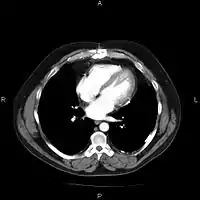

完整的醫療影像儲傳系統可以由不同的醫學影像器材取得影像,如:超音波影像、核磁共振、正子斷層掃描、電腦斷層掃描、乳房攝影與X光攝影等器材。